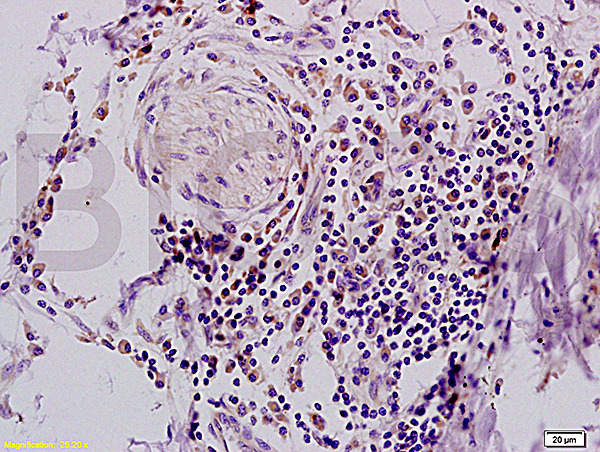

- Main image

- Experimental details

- Formalin-fixed and paraffin embedded human colon carcinoma tissue with Anti-IFABP Polyclonal Antibody, Unconjugated (bs-0788R) at 1:200, followed by conjugation to the secondary antibody and DAB staining

- Sample type

- Human

- Other comments

- Colon